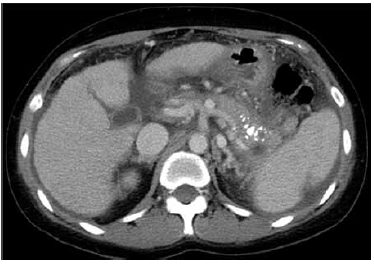

Observe a a tomografia de abdome sem contraste mostrada a seguir:

Considerando a principal alteração encontrada na tomografia de abdome sem contraste apresentada, assinale a alternativa que constitui a hipótese diagnóstica mais provável.